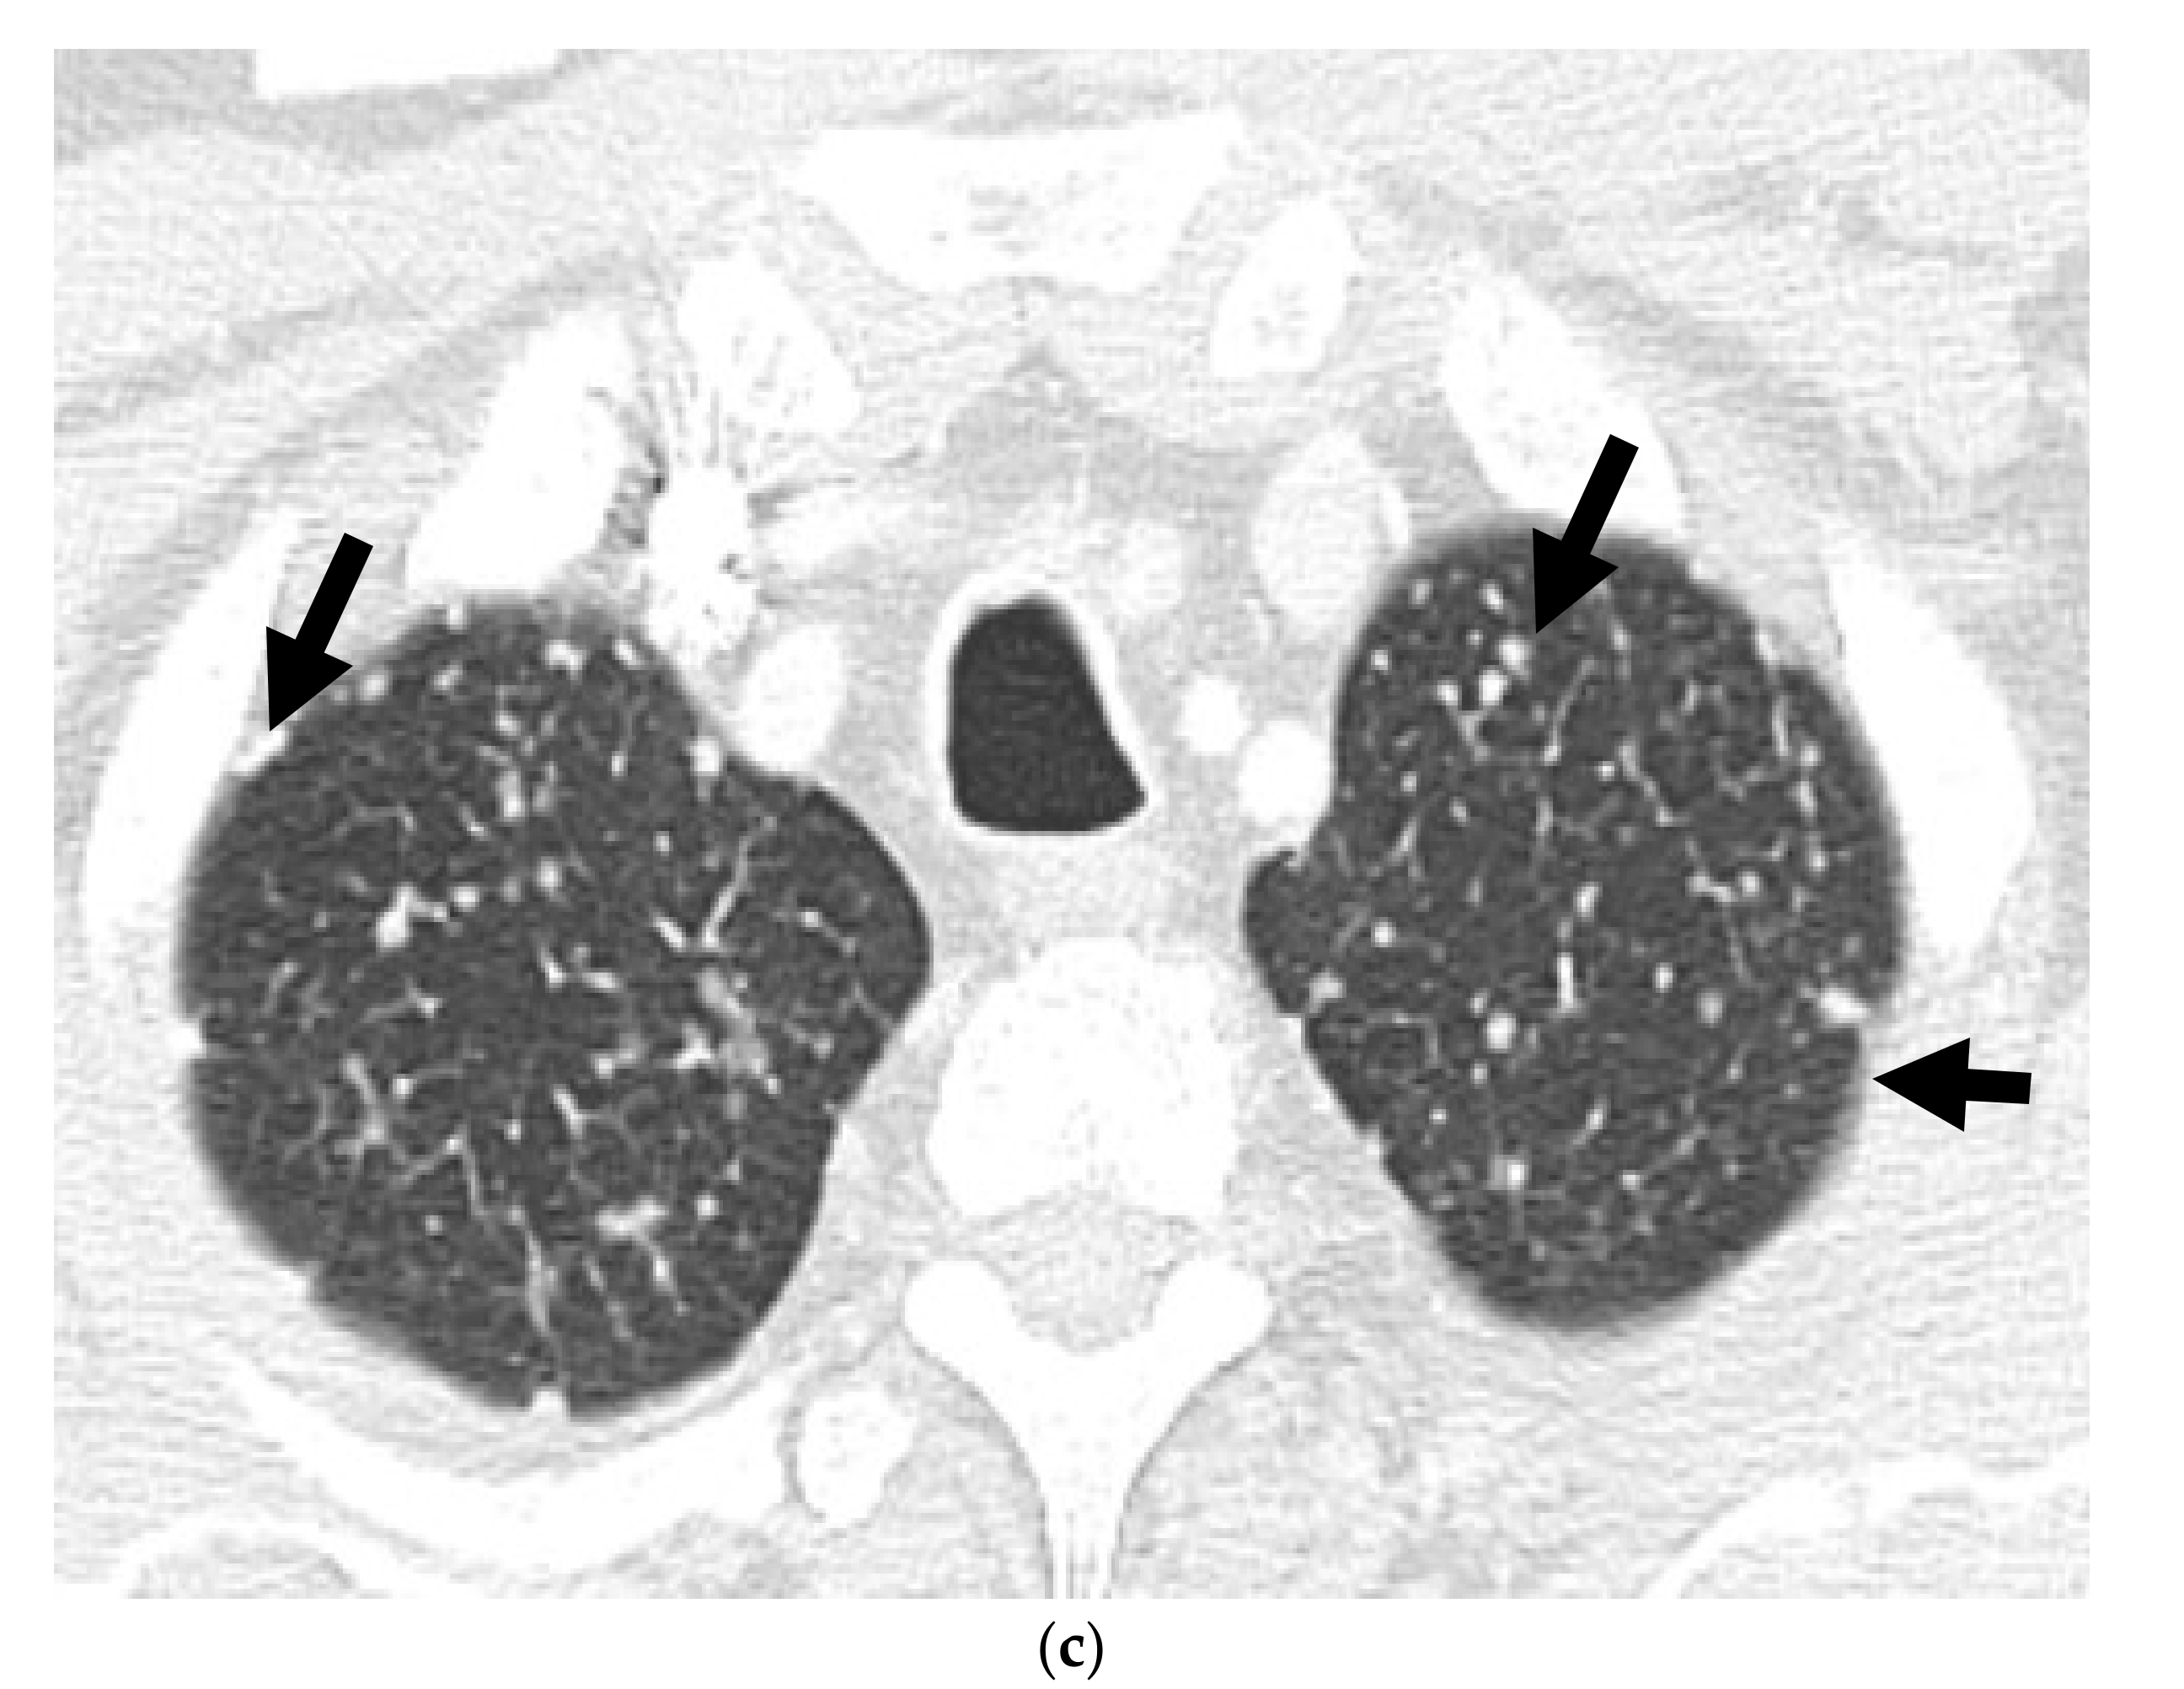

A 60-year-old male with Gleason 9 prostate adenocarcinoma at diagnosis, with later neuroendocrine differentiation after 1 year while on androgen deprivation therapy, with metastatic neuroendocrine prostate cancer. Axial ADC map of the MRI prostate (a) shows hypointense right prostatic nodule (with restricted diffusion), consistent with prostatic cancer (long arrow). There is a large mass along the right posterolateral aspect of the prostate, consistent with extraprostatic extension (short arrow). Axial T1W fast spin echo (FSE) image (b) shows bony metastasis involving the left posterior acetabulum. Patients’ serum PSA decreased following androgen deprivation therapy. Follow up MRI after 7 months revealed improving (smaller) extraprostatic component of the prostatic mass and left acetabular bony metastasis with relatively unchanged size of the prostatic neoplasm on the apparent diffusion coefficient (ADC) map (c) and axial T1W FSE (d) images. However, newly enlarged right presacral node (arrow) seen on T1W FSE (e) of follow-up MRI pelvis and multiple new liver lesions (arrows) seen on CECT (f) at 10 months and 18 months, respectively, after the diagnosis, were biopsied and proven to be metastatic adenocarcinoma with neuroendocrine differentiation.

Multiparametric MRI (mpMRI) is now considered to be the standard imaging evaluation of choice when suspecting prostate cancer. Members of PI-RADS (version 2.1) steering committee recommend using 3T MRI scanners over 1.5T machines for prostatic evaluation, as it increases the signal-to-noise ratio (SNR), leading to an increase in both temporal and spatial resolution. If only 1.5T scanners are available or in the case of inherently low SNR sequences, such as DWI, they recommend the use of endorectal coil (ERC) which has the ability to increase SNR at any magnetic field strength [32]. Most tumors appear isointense to normal prostate tissue on T1-weighted sequences which serve as a baseline for the contrast-enhanced MRI, delineate the prostate outline, and can also demonstrate post-biopsy hemorrhage and periprostatic fat invasion. T2-weighted (T2W) sequences are used to evaluate prostatic zonal anatomy, primarily evaluate the transitional zone or central gland tumors, asses for seminal vesicle or nodal involvement, and detect extra-prostatic extension (EPE). Peripheral zone cancers usually demonstrate ill-defined T2 hypointense focal lesions with restricted diffusion and are primarily evaluated on ADC/DWI images (Figure 1). Transitional zone tumors appear hypointense with spiculated, ill-defined margins and smudgy appearance on T2W images. These lesions may also invade the urethral sphincter and anterior fibromuscular stroma [33,34]. While mpMRI is now considered the technique of choice for initial and local (T) tumor staging, PET/CT and PET/MRI have shown a great value in distant extraprostatic (N and M) staging (Figure 2), restaging after biomedical relapse, and response assessment after androgen deprivation therapy (ADR) [35,36,37,38]. The sensitivity, specificity, positive predictive value, and negative predictive value of multiparametric MRI for detection of EPE (Figure 3), were 48.7%, 73.9%, 35.9%, and 82.8%, respectively [39,40].

There is no core difference in staging between prostatic adenocarcinoma and NEPCs. The TNM staging system, developed by the American Joint Committee on Cancer (AJCC), is the most commonly used staging method to assess the tumor status (T), lymph nodes (N), and metastasis (M) [70]. Unlike prostatic adenocarcinoma, clinical tumor stage 1 is uncommonly seen in cases with NEPC and they usually present with higher stages, with more visceral and nodal metastases with predominantly lytic bone lesions. Hence, NEPC is clinically suspected when a prostate cancer is seen with absent or a low/moderate rise in PSA, presents at advanced stage, or has a predominance of visceral and/or bone metastatic disease (Figure 2). In addition, NEPC is also suspected when the prostate cancer becomes unresponsive to ADT with rapid disease worsening (Figure 3 and Figure 4) [68,69]. Paraneoplastic syndrome is also a potential distinguishing feature for NEPCs, especially SCNC, with Cushing’s syndrome being the most common manifestation [71,72]. Currently, the reference standard for the diagnosis of NEPCs is pathologic examination showing the above microscopic features, plus the presence of neuroendocrine IHC markers, e.g., NSE, SYN, and CgA [16,73].